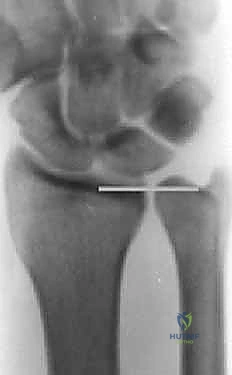

2. التصوير الشعاعي (X-Rays)

تُعد الأشعة السينية ضرورية لقياس "التباين الزندي". يتم أخذ صور بأوضاع محددة (مثل وضعية القبضة المشدودة) لإظهار أقصى درجات الضغط بين الزند والرسغ.

الخطوة 5: التحقق بالأشعة أثناء الجراحة (Fluoroscopy)

لا يترك الدكتور هطيف شيئاً للصدفة. يتم استخدام جهاز الأشعة السينية المباشر داخل غرفة العمليات للتأكد من المحاذاة المثالية للعظم، والوضع الصحيح للشريحة والمسامير، والتأكد من استعادة التباين الزندي المحايد وحل مشكلة الانحشار تماماً.